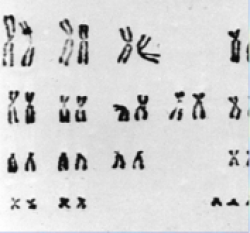

From trisomy 21 gene dosage to developmentally regulated transcription factors

From trisomy 21 gene dosage to developmentally regulated transcription factors

The lab. has previously focused on research aims to understand “Gene-Dosage” effects in trisomy 21 (see below Trisomy 21 Gene Dosage Effect). Currently most of our studies focus on the biology of two members of to the RUNX transcription factor family; Runx1 and Runx3. Of note, an on-going controversial debate about the expression of Runx3 in epithelial cells and its function as tumor suppressor gene (TSG) is summarized in a separate section entitled: “The RUNX3 TSG Conundrum”

The RUNX genes arose early in evolution and maintained extensive structural similarities in mammals. While RUNX1 reside on chromosome 21 and involves in Down syndrome leukemia, Runx3 resides on human chromosome 1p36.1; a region harboring several genes involved in important human diseases. To investigate the biological role of Runx3, we generated Runx3-deficient mice (Runx3-/-). The phenotypes encountered by these mice revealed the crucial importance of Runx3 in development of proprioception and homeostasis of gut immunity. Accordingly, Runx3-/- mice encounter severe congenital limb ataxia, due to premature death of the dorsal root ganglia (DRG) proprioceptive neurons. Similarly, Runx3-/- mice spontaneously developed airway and gut inflammation due to abnormal function of mononuclear phagocytes (MNP).